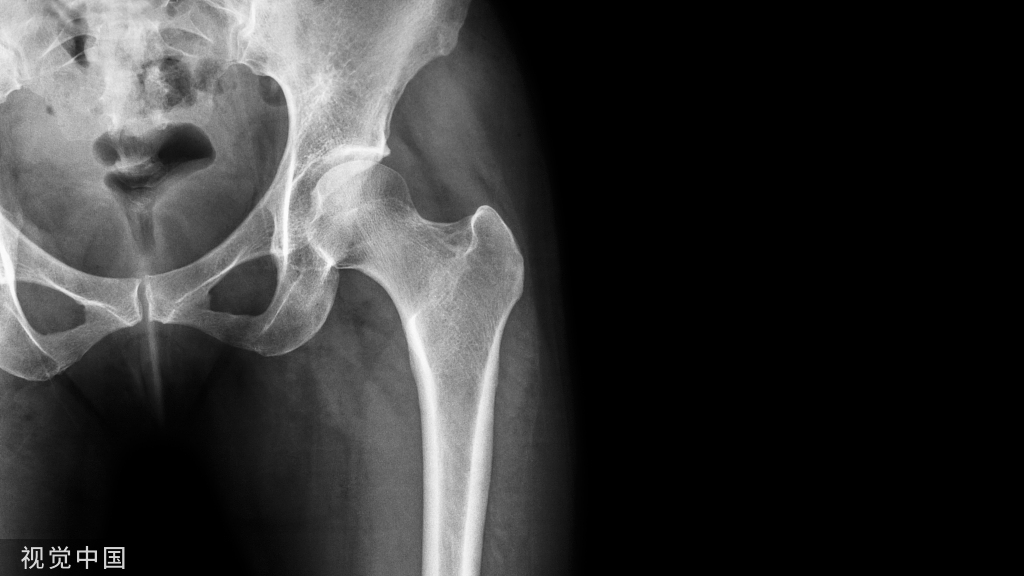

图6:A和B,一位69岁男性假体周围骨盆骨溶解,无骨水泥全髋关节置换术后12年的大转子和小粗隆的右髋位X线片。A:翻修手术前的x光片。B组:髋臼假体翻修一年后行大转子切开复位内固定,2根张力带钢丝和1根斜环扎钢丝,辅以异体骨移植,显示大转子骨折愈合。